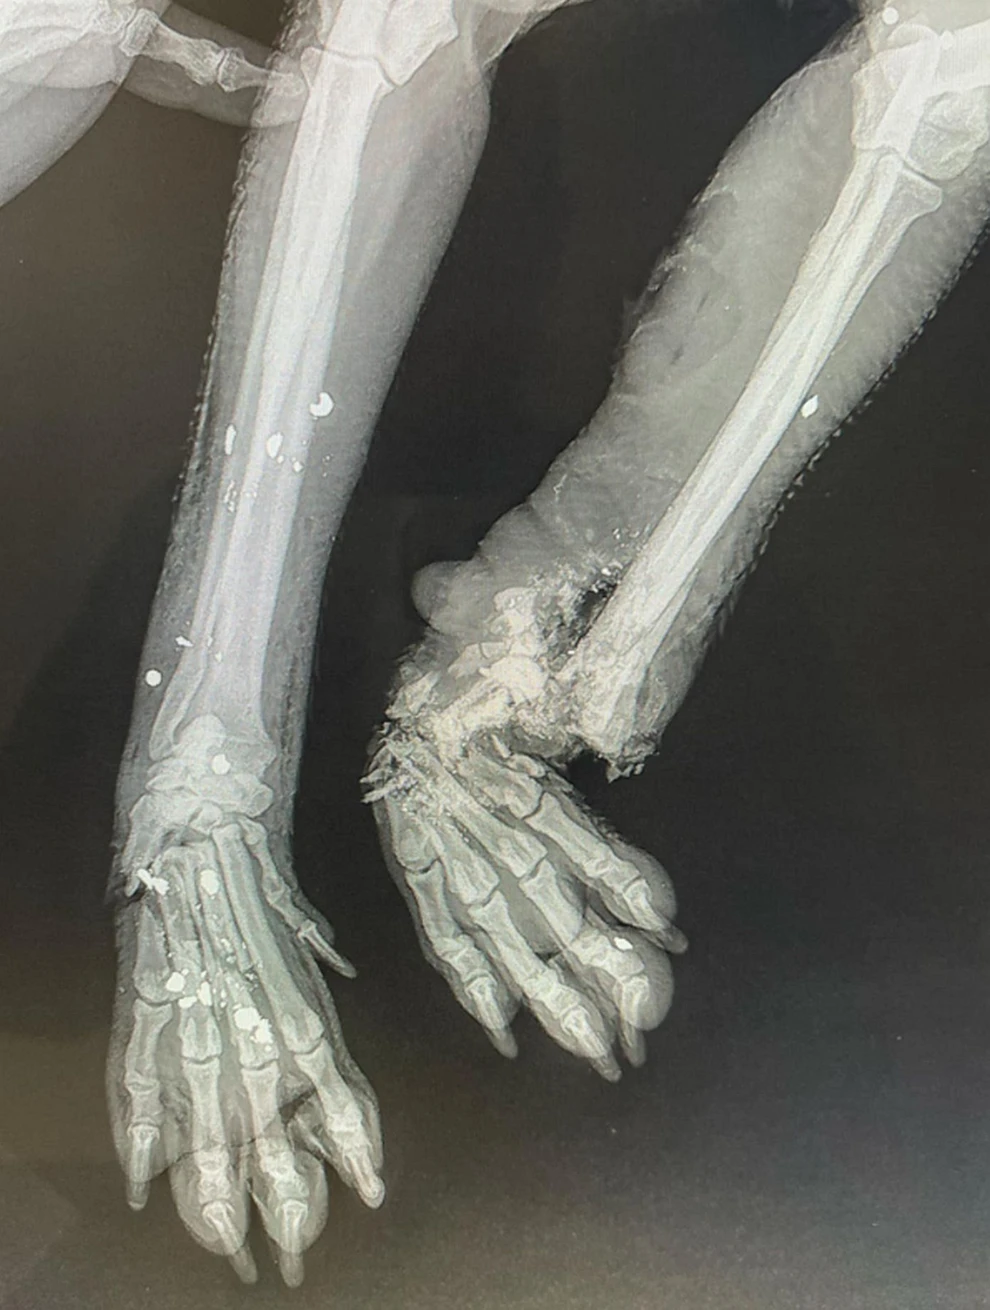

Η μικρόσωμη σκυλίτσα, η οποία από θαύμα είναι ακόμη ζωντανή, βρέθηκε σοβαρά χτυπημένη, με τα κόκκαλα στο ένα της πόδι να είναι κυριολεκτικά θρυμματισμένα, ενώ στο άλλο πόδι το κόκκαλο φαίνεται εκτεθειμένο. Παράλληλα, στο σώμα της βρέθηκαν και σκάγια, τα οποία επιβεβαιώνουν πυροβολισμό!

Ο δράστης της ακραίας κτηνωδίας παραμένει άγνωστος, τη στιγμή που η δίχρονη σκυλίτσα, με τρία πόδια πλέον, παλεύει να επανέλθει.

Έτσι την κατάντησες κτηνος!Ελπίδα, 2 ετών, 10 κιλά χτυπήθηκε από ένα κτηνος, της θρυματισε το ένα πόδι το άλλο σε ναρθηκα και θα δουν αν θα γίνει λειτουργικό, τα 2 πίσω πατάνε με δυσκολια, στο ένα της έβγαλε το κοκαλο και κόπηκε όσο περισσευε. Στο τέλος την πυροβόλησε έχει σκάγια μέσα της!θελουμε:💥Δίχτυ για επιθέματα, γάζες, betadine scrub, famactive silver spray💥ΑΡΚΑΛΟΧΩΡΙ 2025ΧΩΡΙΟ ΣΤΗΝ ΚΡΗΤΗΝΕΚΡΑ ΑΚΡΩΤΗΡΙΑΣΜΕΝΑ ΠΑΡΑΛΗΤΑΠεριμένω να με μπλοκάρει τώρα το FB!